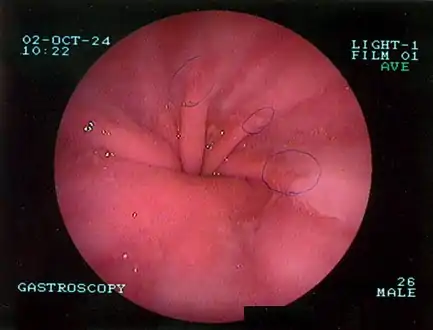

The diagnosis of a hiatal hernia is typically made through an upper GI series, endoscopy, high resolution manometry, esophageal pH monitoring, and computed tomography (CT). Barium swallow as in upper GI series allows the size, location, stricture, stenosis of oesophagus to be seen. It can also evaluate the oesophageal movements. Endoscopy can analyse the esophageal internal surface for erosions, ulcers, and tumours. Meanwhile, manometry can determine the integrity of esophageal movements, and the presence of esophageal achalasia. pH testings allows the quantitative analysis of acid reflux episodes. CT scan is useful in diagnosing complications of hiatal hernia such as gastric volvulus, perforation, pneumoperitoneum, and pneumomediastinum.[8]